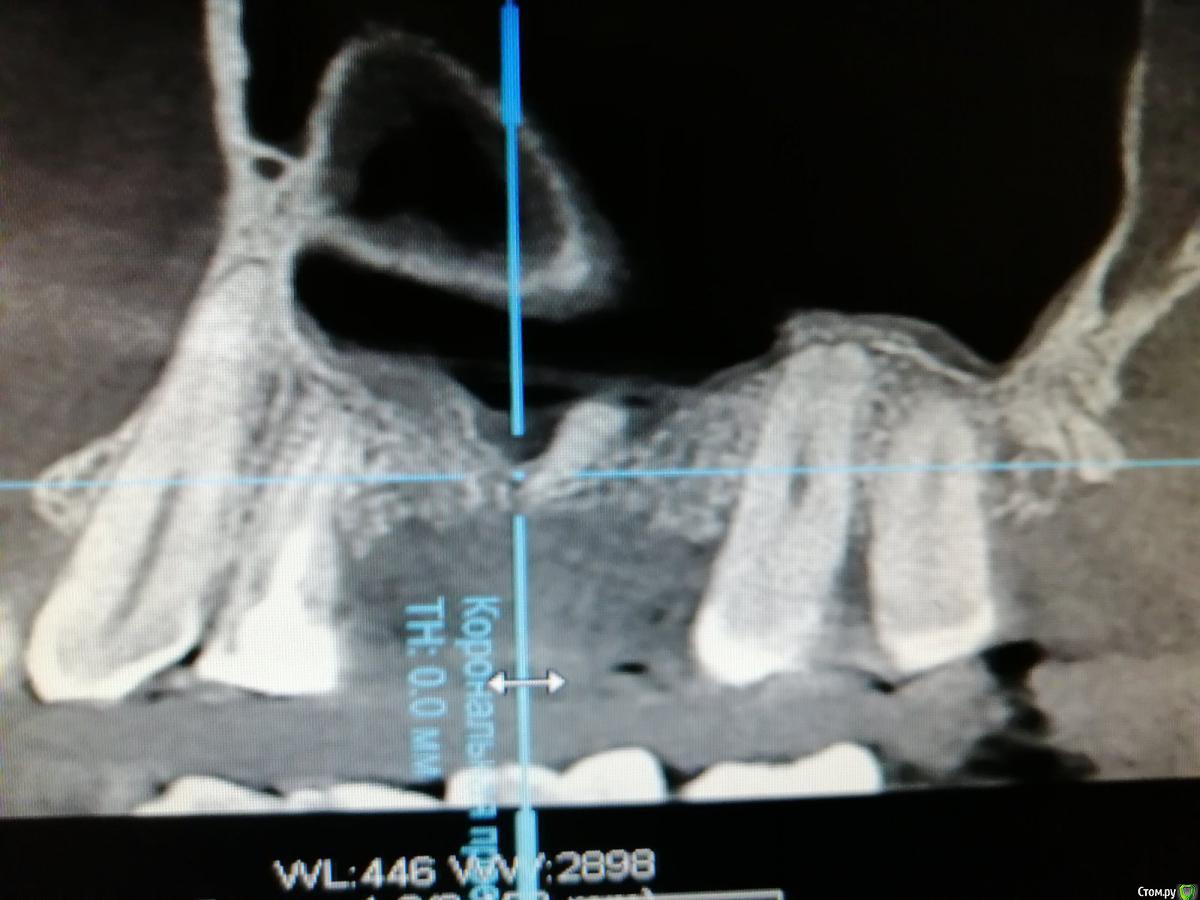

Добрый день. Встал вопрос об имплантации. Были удалены 5 и 6 зубы верхней челюсти. После удаления ничего не беспокоило. Все затянулось десной. через 3 мес. новое КТ. На снимке видно твердое тело в гайморовой пазухе. Врач(не тот который удалял) сказала, что мне надо обращаться к лору. Посоветуйте что делать? Меня не беспокоит челюсть. Дышу я хорошо.

Никаких ощущений нет плохих. Можно будет обойтись без госпитализации? Первый снимок до удаления и два спустя 3 мес после удаления.

Не надо к лору, надо синус лифт делать и в процессе этой операции оставшийся фрагмент удалить, для врача с богатым опытом проведения имплантации в этой области сложностей с этим быть не должно